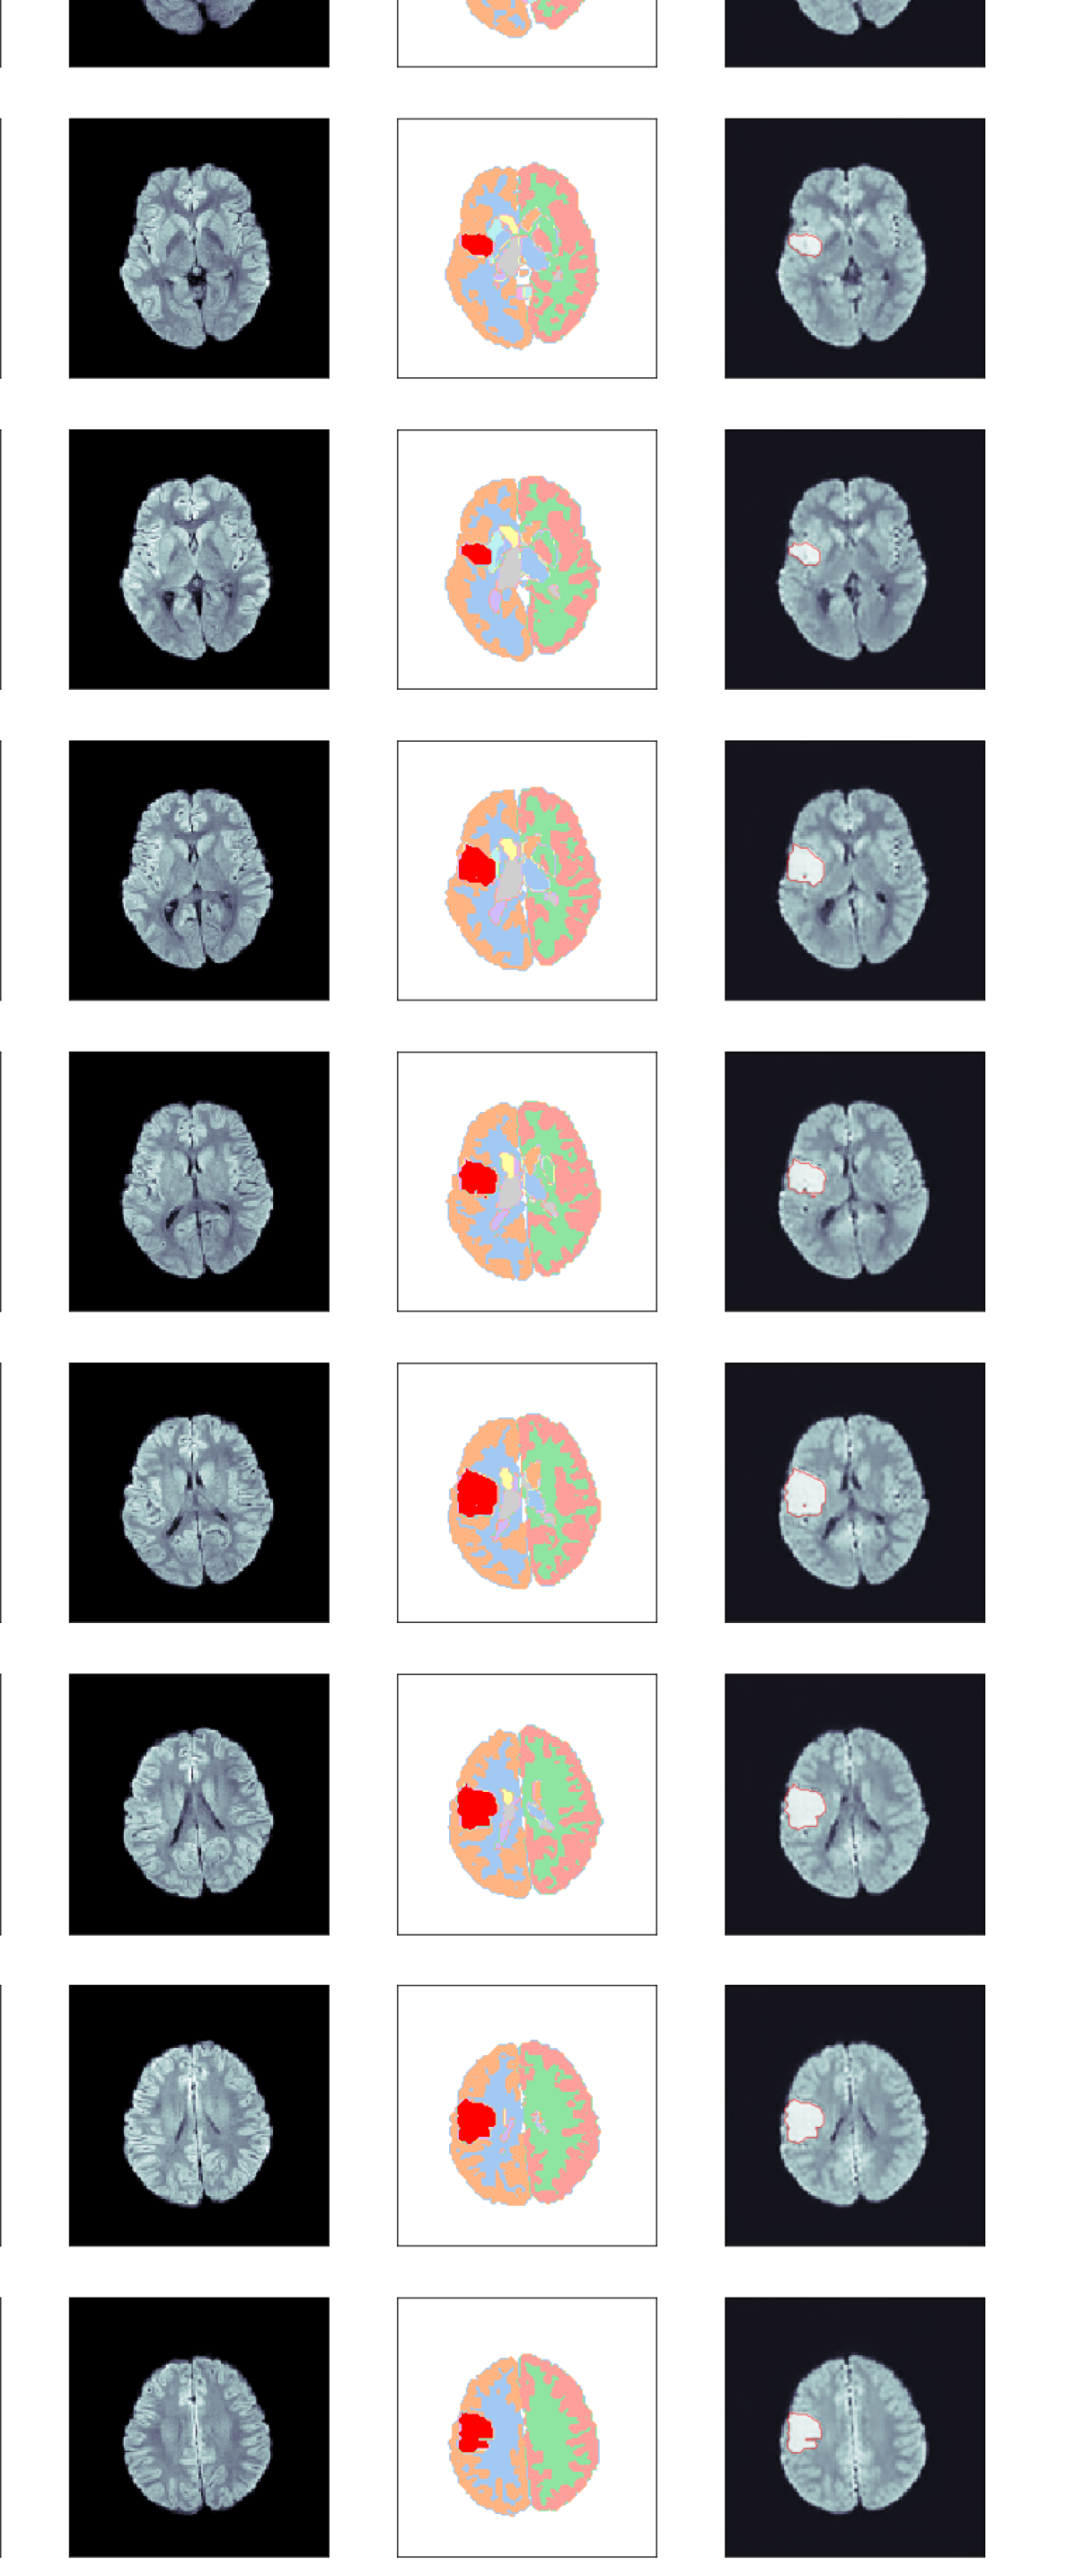

The generated segmentation map is subsequently decomposed into 2D slices and fed into the ITM in order to generate a fake DWI. In this manner we obtain a database of 2027 fake DWIs per ITM. Fig. 2 shows an example of this lesion implantation procedure, which is also sketched in the graphical abstract. The left column shows the healthy input DWI volume, whose corresponding semantic segmentation map is shown next to it. The third column shows the segmentation map after implanting a lesion label according to the output of the GAN. Subsequently, we have generated realistic DWIs from axial slices of these 3D segmentation maps using three ITMs, namely Pix2Pix, SPADE and cycleGAN, as shown in the right-most column for one axial slice.

Fig. 4 shows some examples of generated images. The synthetic DWIs generated by the ITMs display anatomical structures that are coherent in location, shape, and size across the volume, including the lesions. The first two images from the left have been generated using Pix2Pix. Panel (a) was generated using a reconstruction loss weight , while Panel (b) was created using . The results are of good quality, subjectively realistic and, as anticipated, come accompanied by a high-fidelity lesion label. Only closer inspection of a number of volumes reveals that the larger reconstruction loss weight produces slightly sharper images with more details both inside the lesion and in the brain tissue. We have therefore tested both models quantitatively in the following section.

The lesion intensity produced by SPADE [Fig. 4(c)] is noticeably lower than in the images generated by Pix2Pix, but also the contrast outside the lesion is much lower: in the posterior part of the synthetic brain, barely any gray/white matter contrast is present. While this might seem a disadvantage at first sight, it could actually be beneficial for training a U-Net to reliably detect lesions with lower signal increase.

Next, notice that cycleGAN has failed to recognize and synthesize any lesion hyper-intensity, while producing very high inter-tissue contrast [Fig. 4(d)]. We have experimented with fine-tuning the model on IS data, training on IS data alone, and modifying the network architecture; however, this result seems to be unavoidable. We speculate that this is closely related to the cycle consistency requirement of cycleGAN, i.e. that the two generators map an image back to itself as close as possible, and large class imbalance between lesion and non-lesion voxels. Similarly, Ref. cycleGAN identified ‘failed cases’ which indicate that cycleGAN generalizes poorly. Due to this failure, we have excluded cycleGAN from the quantitative analysis, and leave a dedicated study using cycleGAN for data augmentation for future work. We stress that this does not preclude any application of cycleGAN to this task; however, it will require an approach that differs from the one chosen here, and thus the comparability of ITMs is not given.